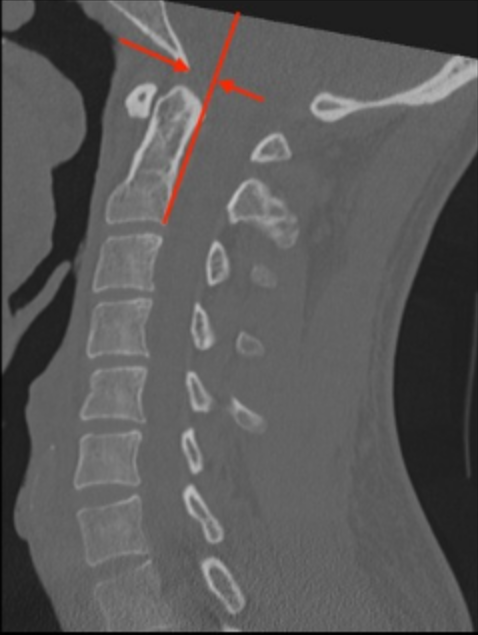

CT Scan

• Use a midsagittal CT image.

• Draw a vertical line along the posterior cortex of the C2 vertebral body. Extend this line superiorly past the dens and into the cranial vault. Note: This line follows the body, not the dens.

• Identify the basion point.

• Measure the horizontal distance from this line to the basion.

• Determine Sign:

• If the basion is anterior to the PAL, the value is positive.

• If the basion is posterior to the PAL, the value is negative.